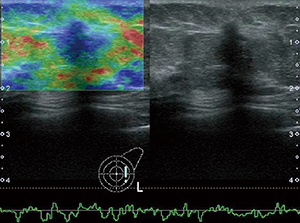

●Shear wave with Smart maps

プローブを静止した状態で,組織を圧迫することなく組織の硬さの絶対値を求めることができます。プローブからのPush Pulseによってせん断波を発生させ,その伝搬速度をカラーマッピング表示することにより,硬さの空間的分布を表示できます(図1)。これに加え,せん断波の到達時間を等高線表示する東芝独自の表示モードにより,せん断波の伝播状態を確認して検査結果の信頼性を判断することができます(図2)。

図1 カラーマッピング表示 |

図2 等高線表示 |

| (図1,2画像ご提供:兵庫医科大学・飯島尋子先生) | |